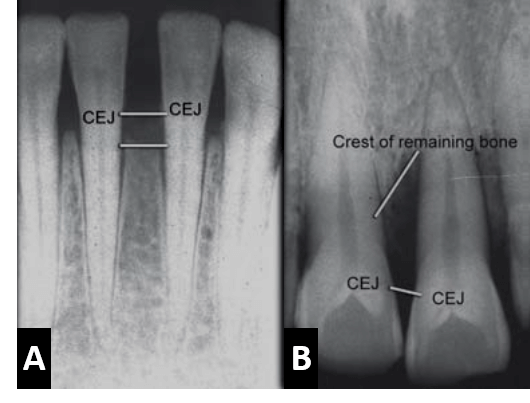

La pérdida ósea atribuida a la enfermedad periodontal puede ser estimada como la diferencia entre la altura ósea fisiológica y la altura de hueso remanente. Cuando está perdida ósea ocurre en áreas aisladas abarcando menos del 30% del hueso de soporte es llamada perdida ósea localizada; mientras que cuando el compromiso óseo se presenta en ambas arcadas dentarias de forma general tanto en la arcada superior como en la inferior con más del 30% de compromiso del hueso de soporte es descrito como una pérdida ósea generalizada. Así también, cuando la pérdida ósea forma un ángulo con un plano imaginario entre la unión cementoadamantina de dos dientes adyacentes, es conocida como reabsorción ósea de tipo vertical o angular; y cuando la perdida ósea se observa de forma paralela con el plano imaginario entre la unión cementoadamantina de dos dientes adyacentes, se conoce como reabsorción ósea de tipo horizontal.